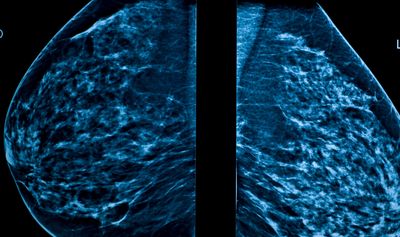

Mammography is a specialized medical imaging technique that uses low-dose X-rays to detect early signs of breast cancer, even before symptoms appear. It plays a critical role in early detection, which increases the chances of successful treatment and survival.

🔍 Types of Mammograms

- Screening Mammogram

- For women without any symptoms

- Typically involves 2 views of each breast

- Diagnostic Mammogram

- For women with lumps, pain, or nipple discharge

- More detailed images from different angles